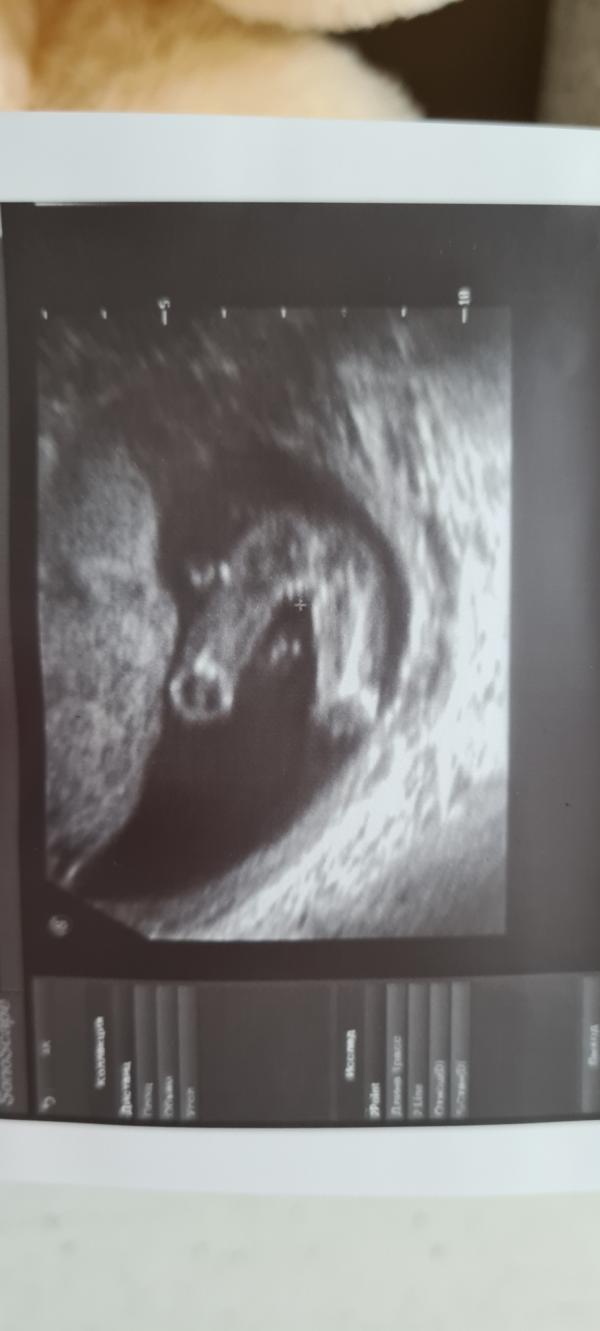

Сегодня сходили на УЗИ ,мы ждем девочку🌸